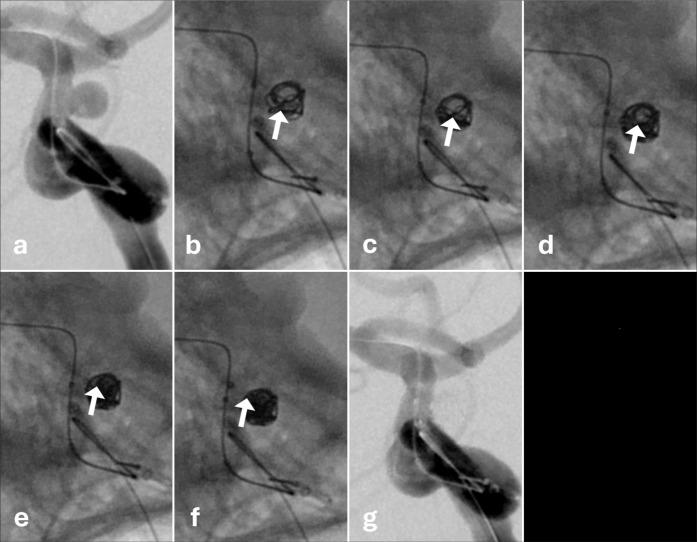

Background: Coil embolization for cerebral aneurysms is an important technique and is not likely to be replaced in the foreseeable future. Recently, the Target Tetra detachable coil (TTDC) has become available, thereby raising expectations for a safer embolization in small aneurysms. Based on our experience, we report the behavioral characteristics and effective utilization of TTDCs.

Methods: We analyzed 28 patients who underwent surgery using the TTDC for intracranial aneurysms between December 2023 and November 2024.

Results: Five cases were treated using the TTDC only. In four of five cases, the aneurysm height was <3 mm. In terms of complications, intraprocedural rupture occurred in two cases and thrombosis in two. None of the patients presented with delayed hemorrhage during the follow-up period.

Conclusion: The TTDC coils cluster at the tip of the microcatheter. Thus, effective embolization can be achieved by filling from the deeper available space. Based on the behavioral characteristics of TTDCs, it is not only beneficial as a finishing coil but also plays a role in filling. We believe that TTDCs may be a useful option for embolizing small aneurysms, including ruptured ones that were previously challenging to treat, and cases in which microcatheter stability are compromised.